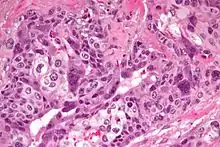

| Micrograph of choriocarcinoma showing both of the components necessary for the diagnosis - cytotrophoblasts and syncytiotrophoblasts. The syncytiotrophoblasts are multinucleated and have a dark staining cytoplasm. The cytotrophoblasts are mononuclear and have a pale staining cytoplasm. H&E stain. | |

Characteristic feature is the identification of intimately related syncytiotrophoblasts and cytotrophoblasts without formation of definite placental type villi. Since choriocarcinomas include syncytiotrophoblasts (beta-HCG producing cells), they cause elevated blood levels of beta-human chorionic gonadotropin.

Syncytiotrophoblasts are large multi-nucleated cells with eosinophilic cytoplasm. They often surround the cytotrophoblasts, reminiscent of their normal anatomical relationship in chorionic villi. Cytotrophoblasts are polyhedral, mononuclear cells with hyperchromatic nuclei and a clear or pale cytoplasm. Extensive hemorrhage is a common finding.